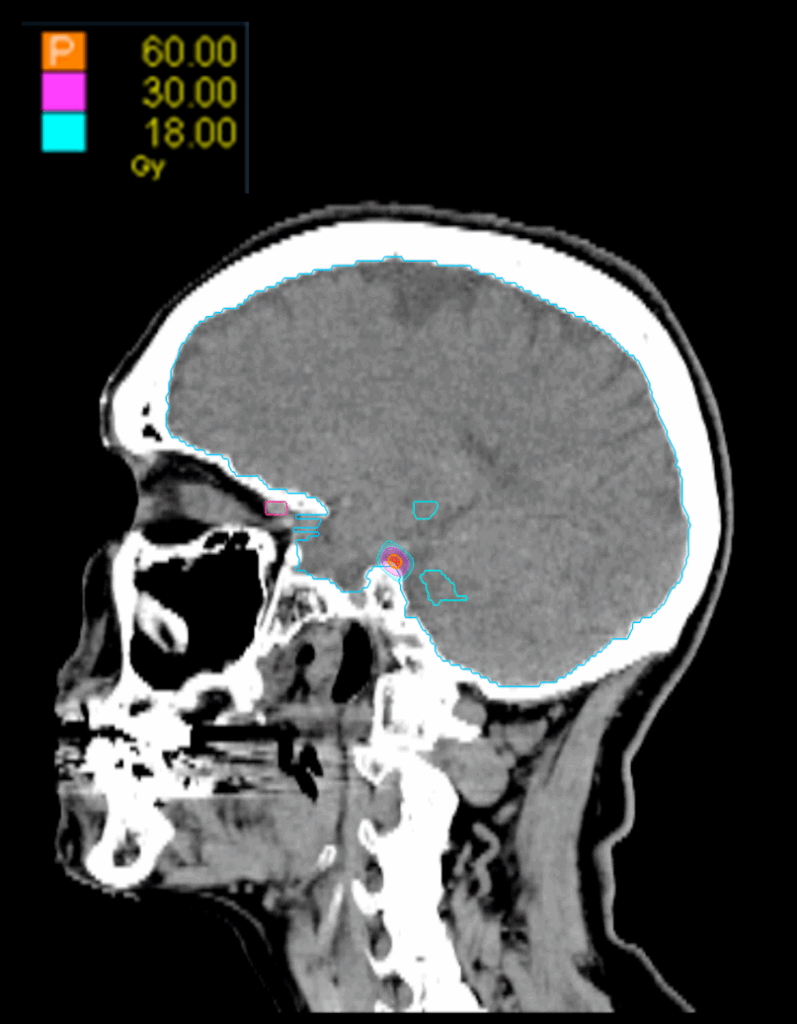

Treatment Plan Images

Treatment Planning Highlights

Fractionation

60 Gy in 1 fraction

PTV(s) Volume

PTV, 0.01cc

Dose Distributions

- Prescription to the 80 % isodose line

- Max. dose 75 Gy

Collimator

Fixed 5mm

Dose Calculation Algorithm

Ray-Tracing